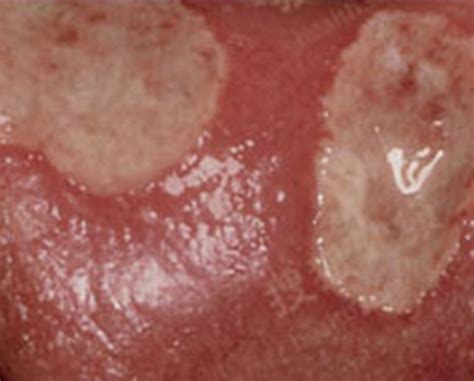

皮肤病药